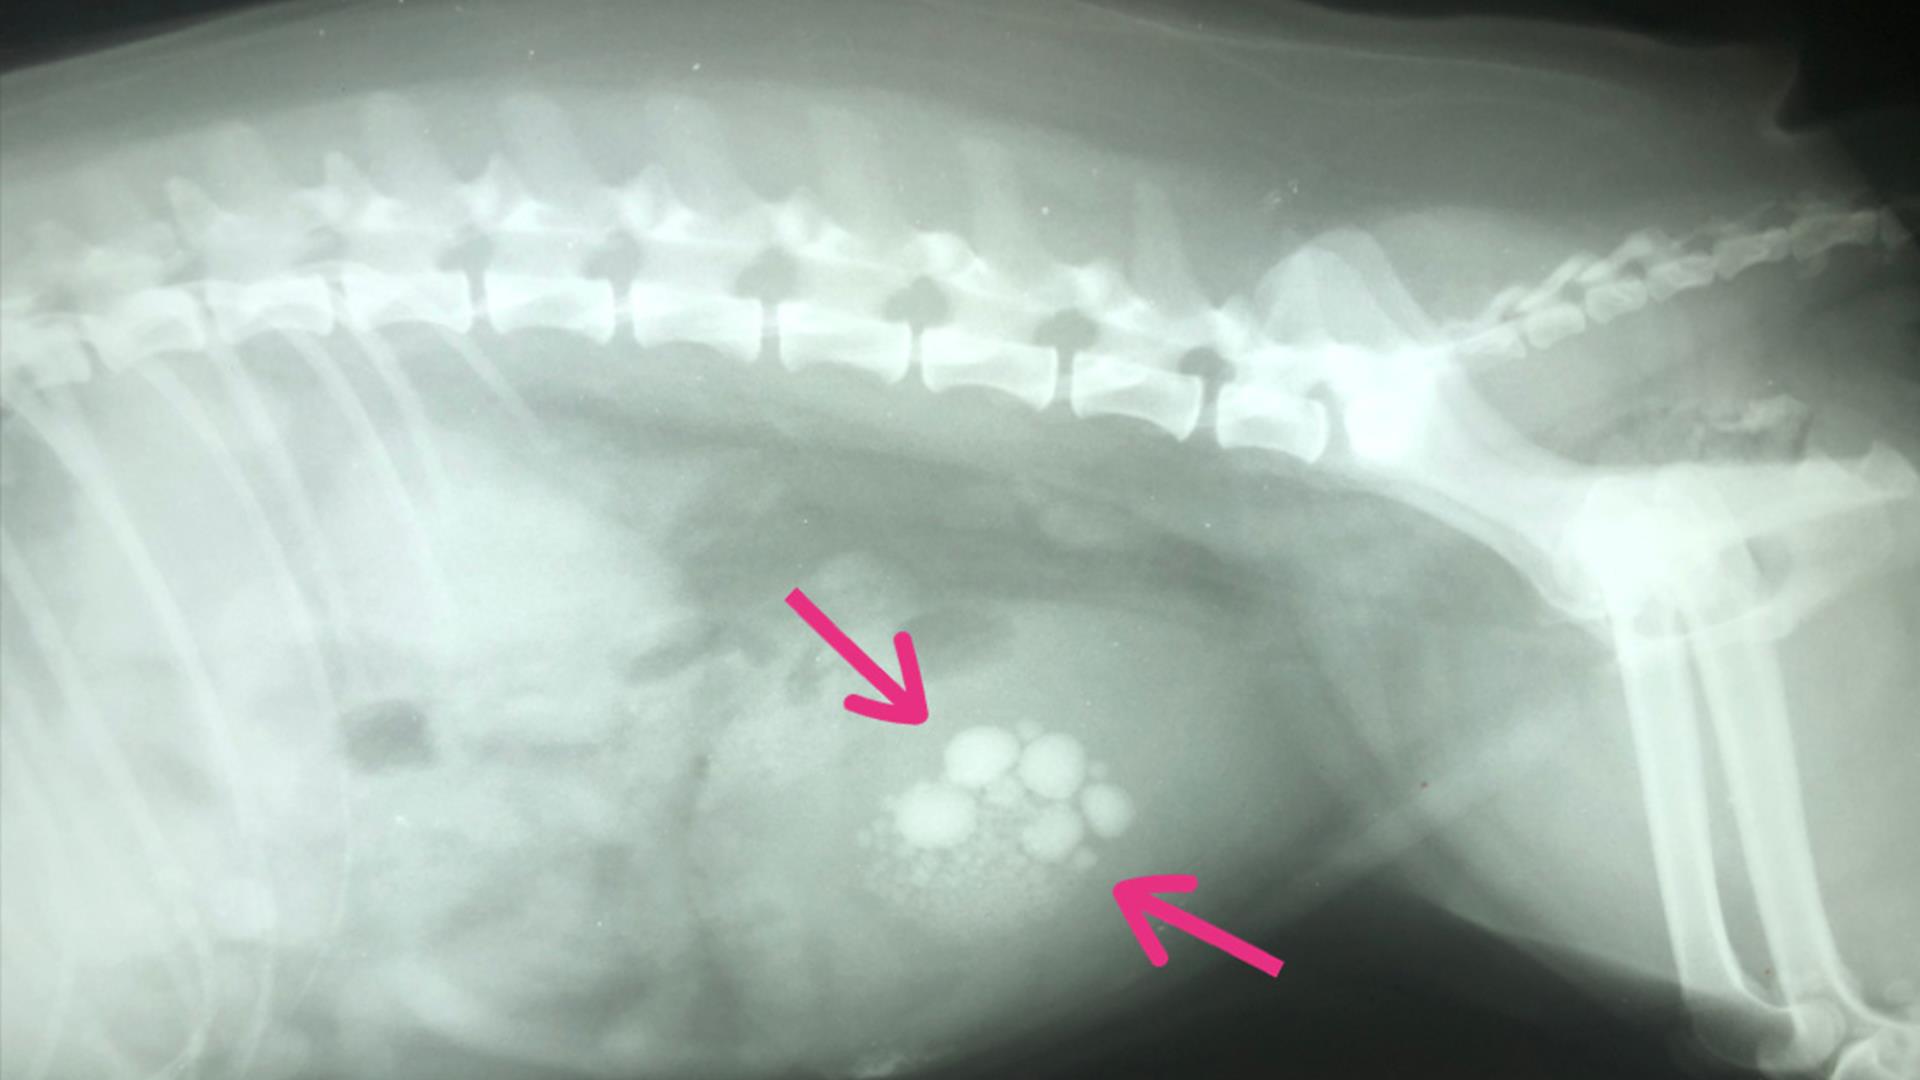

Your vet will ask you some questions about your dog and will feel your dog’s tummy. If they have large bladder stones your vet may be able to feel them, but it’s likely that they will need to carry out further tests, such as X-rays or an ultrasound of the bladder to confirm. A special dye is sometimes injected into the bladder to make the stone appear bright on x-rays.